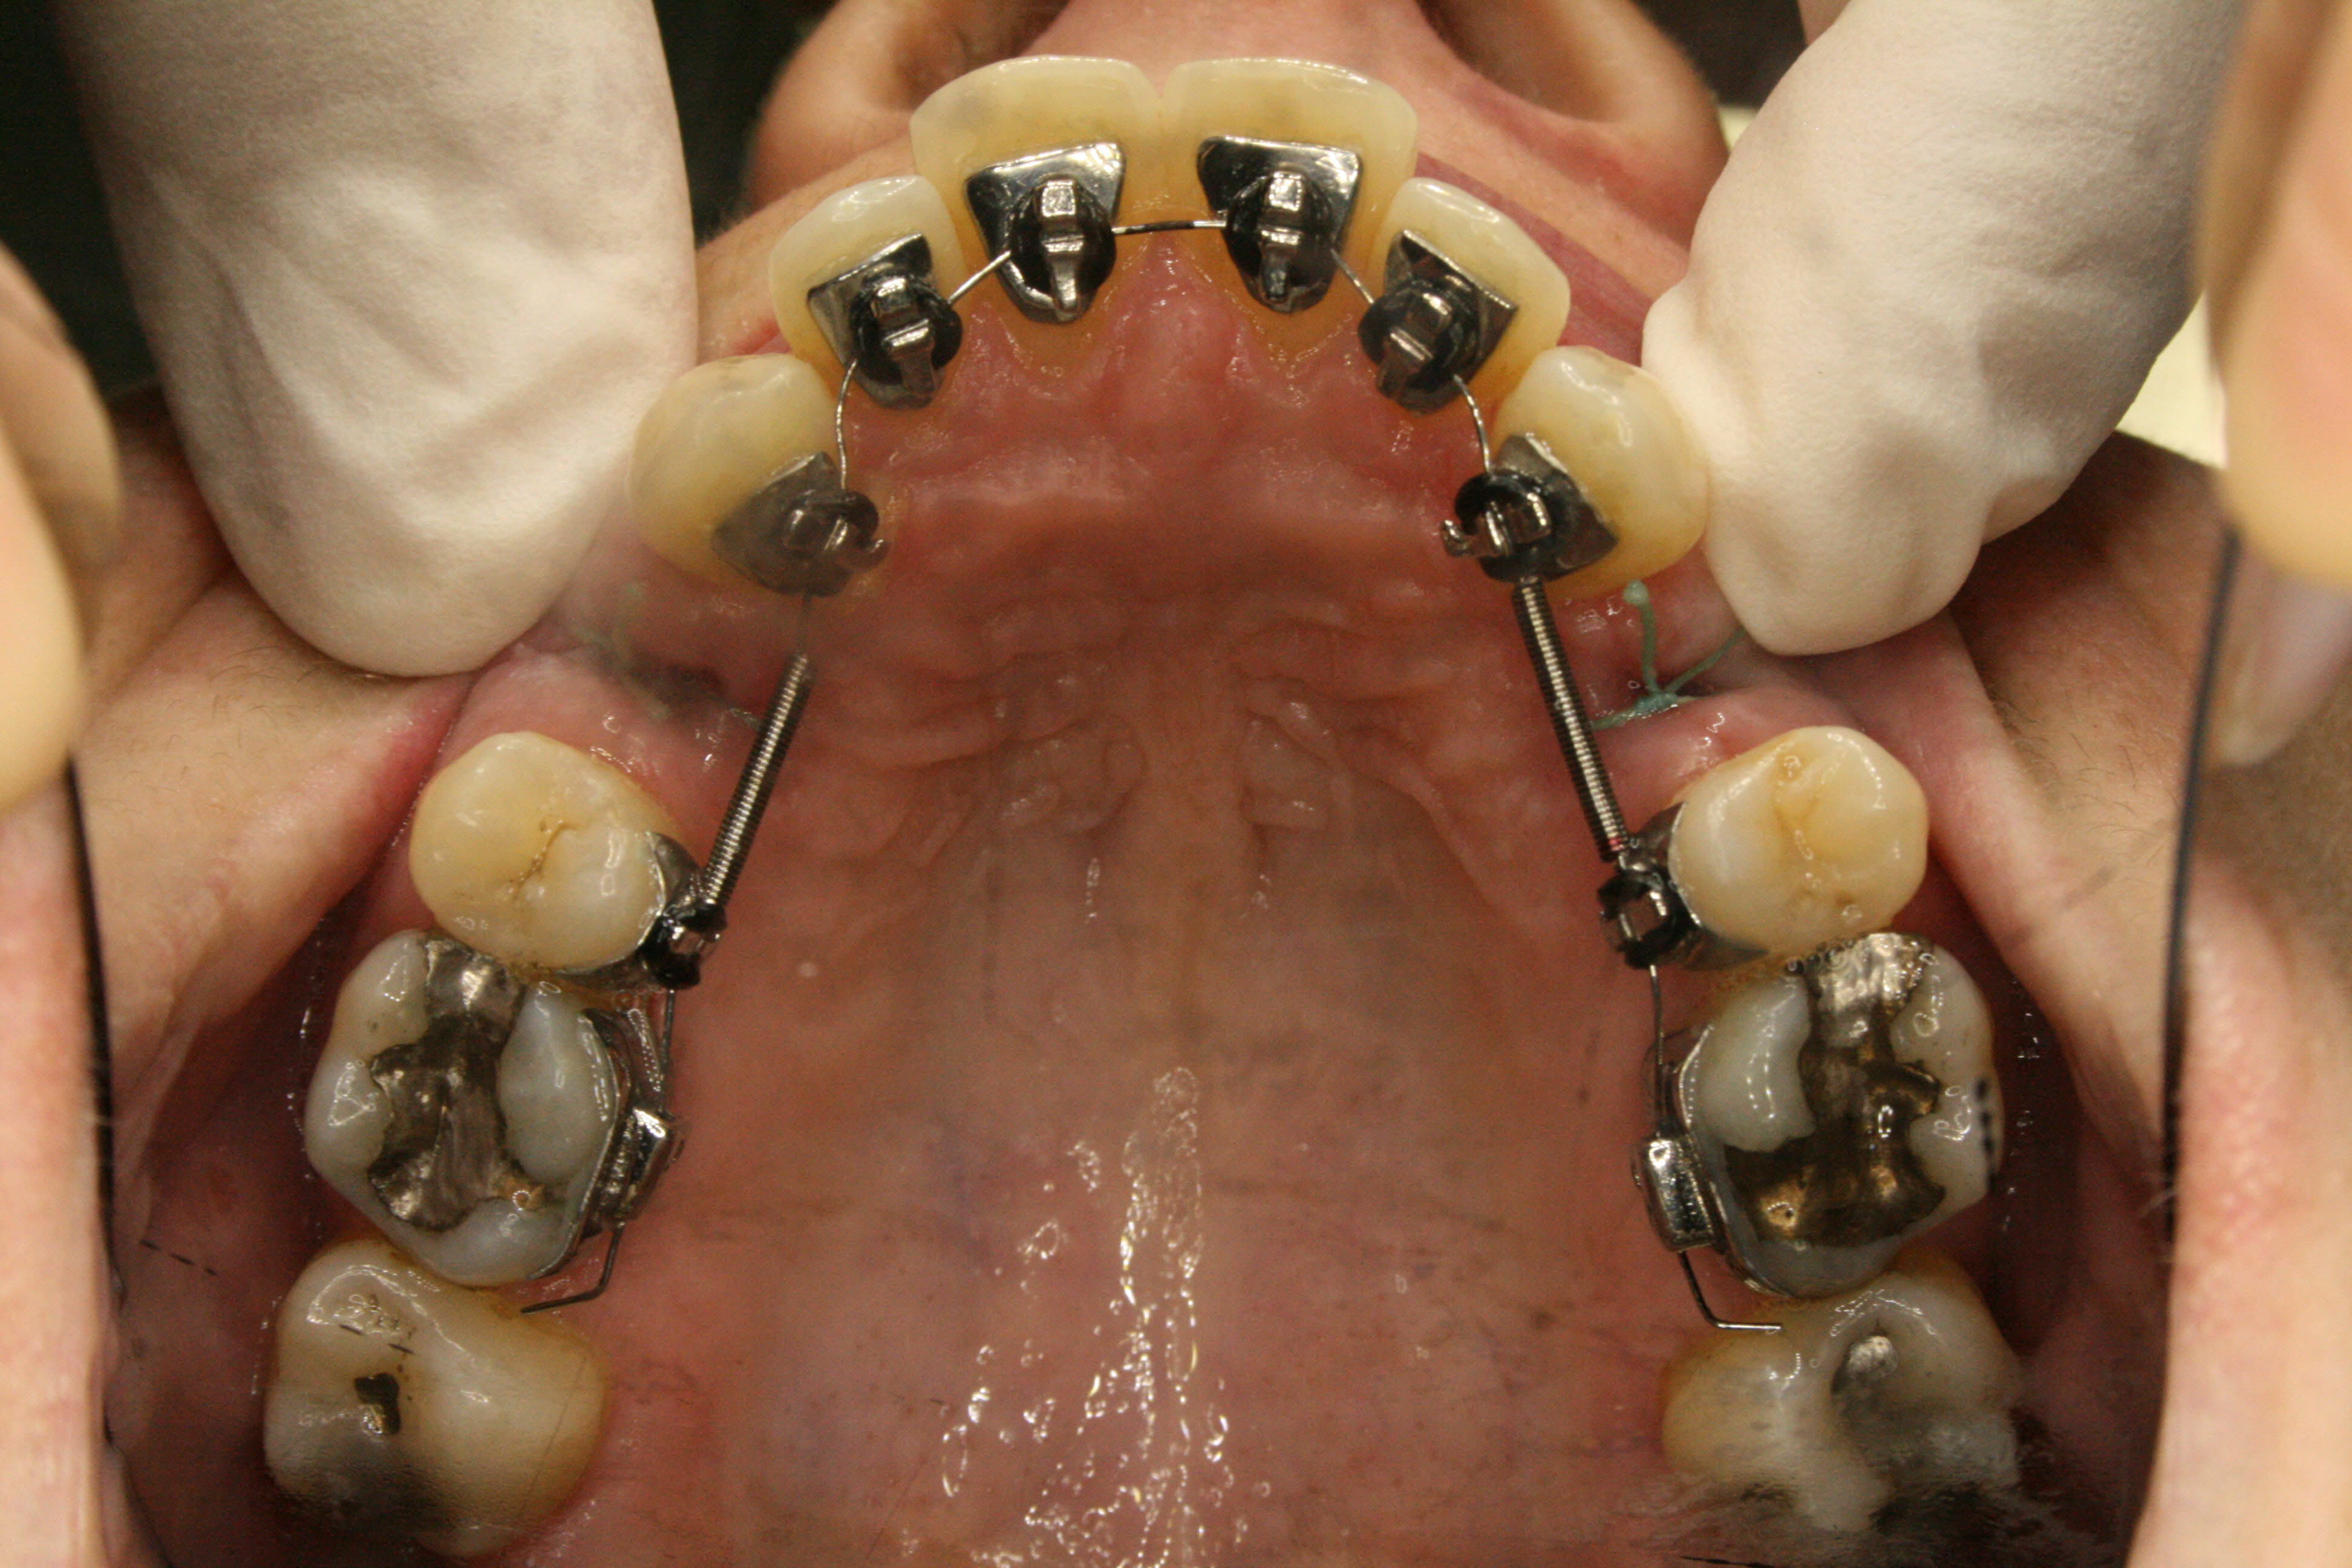

Die ersten kleinen Backenzähne sind bereits entfernt und die festsitzende Zahnspange ist eingesetzt, in diesem Falle quasi unsichtbar auf der Innenseite der oberen Schneidezähne. Es ist wesentlich, daß die Lücken nur von vorne her geschlossen werden. Dies wurde sichergestellt, indem die Zähne hinter den Lücken über temporäre kleine Implantate am Gaumendach verankert wurden. In der Bildsequenz ist der Behandlungsfortschritt zu erkennen; der Lückenschluß war nach 1½ Jahren erreicht.

Im Unterkiefer kam auch eine auf der Innenseite der Zähne befestigte Zahnspange zum Einsatz; da es keine Lückenschlußaufgabe zu bewältigen gab, konnte ein einfacheres System verwendet werden. Es ist angenehmer für die Zunge, weil es flacher ist als das aufwendigere System im Oberkiefer. Siehe hierzu auch die Ausführungen im Abschnitt „Behandlungsmethoden – Welche Arten von Zahnspangen gibt es". Die Ausformung des Unterkiefers war nach einem Jahr und 2 Monaten abgeschlossen.